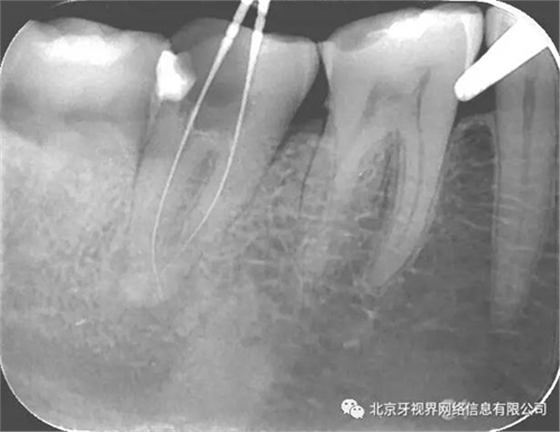

2次復診常規(guī)根備加根充(AH-plus糊劑加牙膠尖根充)

最后附帶近期彎曲根管的圖片